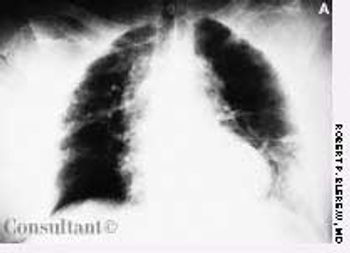

A 71-year-old woman was brought to the hospital with blunt abdominal trauma suffered in an automobile accident. She complained of pain in the chest and abdomen.